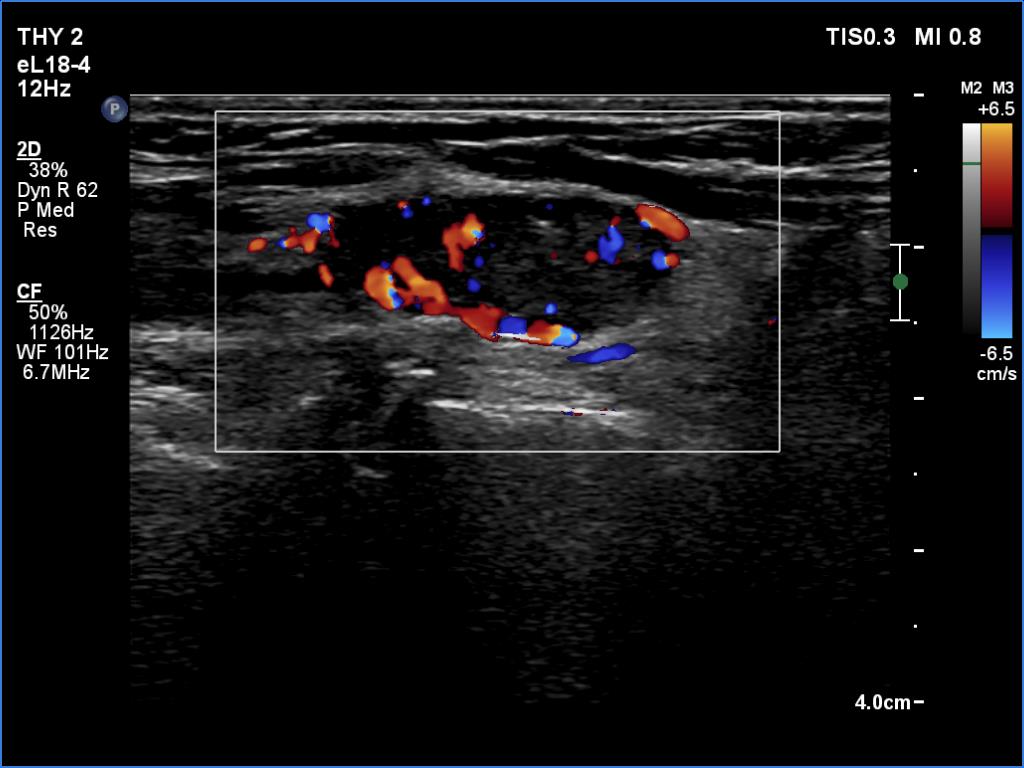

Graves' disease - case 169

Follow-up investigation 6 months after first visit (ultrasonographic picture 7)

Left lobe, longitudinal scan, color Doppler mode. The mass is avascular.